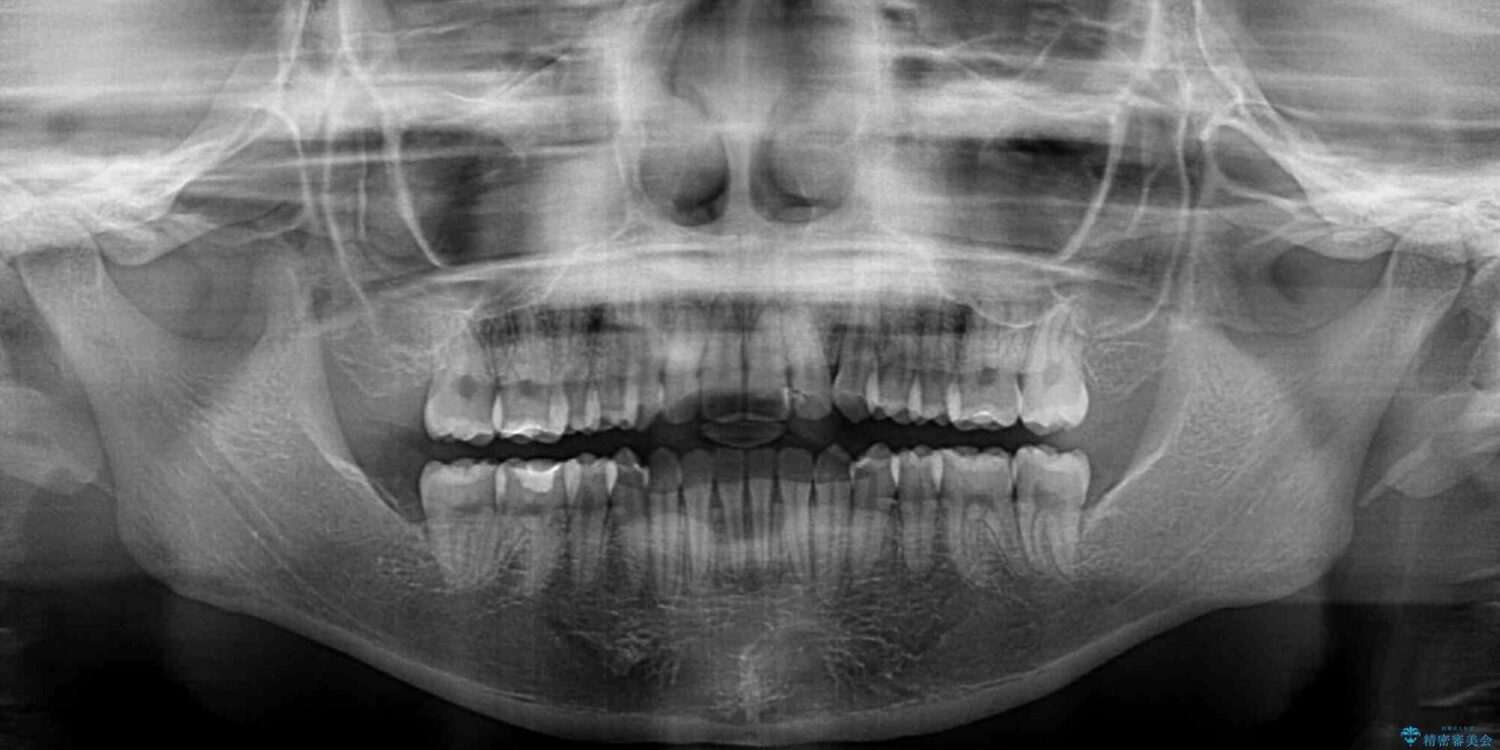

治療前

• 【モニター】短期間で終わりたい ワイヤー装置での非抜歯矯正 治療前画像